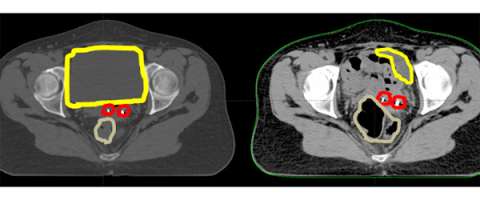

In these cartoons the yellow circle represents the bladder, the red oval represents the vagina, the brown circle represents the rectum, and the blue outline represents the area that will be treated with radiation. The first figure represents a typical example of the radiation field for 3D-conformal radiation. A large enough radiation field is used so we can ensure that all the targets are included with a generous margin. In treating with a larger margin organ motion (ie bladder/rectum being full vs empty) aren’t as relevant because the target will always fall within the radiation field.

So in this cartoon one can see that the target for radiation is really the upper vagina (red oval) and tissues around it and the radiation field in blue is just covering this area with a small margin extending into the bladder and rectum.

Here is an axial CT scan slice of an actual patient with her bladder full on the left and her bladder empty on the right. You can see that with the bladder (yellow) empty that additional bowel falls within the pelvis and that the marker seeds (red) are in a different place (also in part due to increased air in the rectum (brown). This example demonstrates the importance of daily image guidance and making sure that your bladder is consistently full during the course of your treatment.

CT Scan